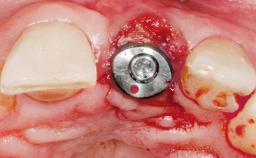

A 36-year-old female patient was referred for the replacement of the upper left central incisor (tooth 21), which had fractured. Although the tooth had been asymptomatic for many years, the crown began to loosen, at which time she presented to her dentist for an assessment. Teeth 21 and 22 had both been endodontically treated many years previously. She was a healthy individual and a non-smoker.

On examination, the patient had a low lip line and only displayed the coronal half of the anterior teeth when smiling.